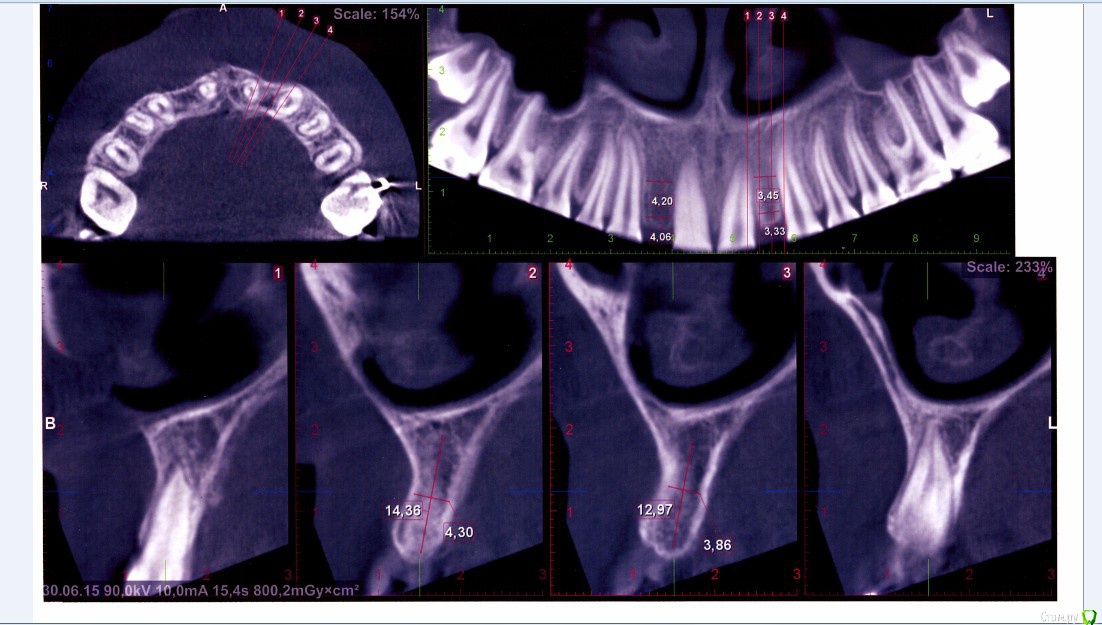

КТ лето 2015г.:post-461-0-66686400-1456407220_thumb.jpgpost-461-0-08014000-1456407222_thumb.jpg